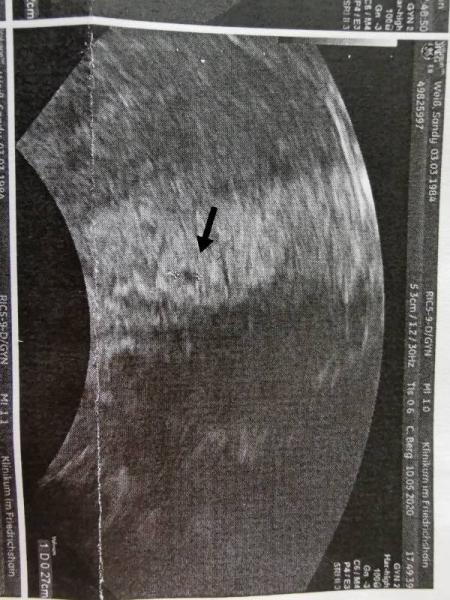

Hallo ihr lieben ich bin Sandy 36 und bereits 3 mal Mama. Die Kinder sind 18/17 und 14 Jahre alt. Ich habe am 06.05. Positiv getestet, nachdem ich im April meine Pille abgesetzt habe. Gestern war ich im Kh weil mir schwindlig war und der Kreislauf rumgesponnen hat und bekam auch noch ein Bild mit. Alles noch sehr klein und auch nur die fruchthöhle aber laut Ärztin soll es 4+5 sein so ungefähr. Termin wäre demnach der 12.01.2021

Bild zu Ich würde mich gern zu euch gesellen - Forum für Januar - Mamis